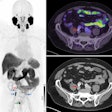

The U.S. Food and Drug Administration (FDA) approved Axumin in 2016 for PET imaging in men who are suspected of having recurrent prostate cancer based on elevated prostate-specific antigen levels that occur after primary treatment. The radiotracer contains a fluciclovine amino acid labeled with an F-18 radioisotope that reveals increased cellular activity in glial cells in tumors. It is currently being investigated for other potential clinical uses.

Graphical abstract. Image courtesy of the Journal of Nuclear MedicineThe researchers enrolled 30 glioblastoma patients with radiographic progression after first-line chemoradiotherapy who were planned for surgery. Patients underwent preoperative F-18 fluciclovine PET and MRI, with differences in PET radiotracer uptake between the types of tumors compared to results confirmed by biopsy lab tests.